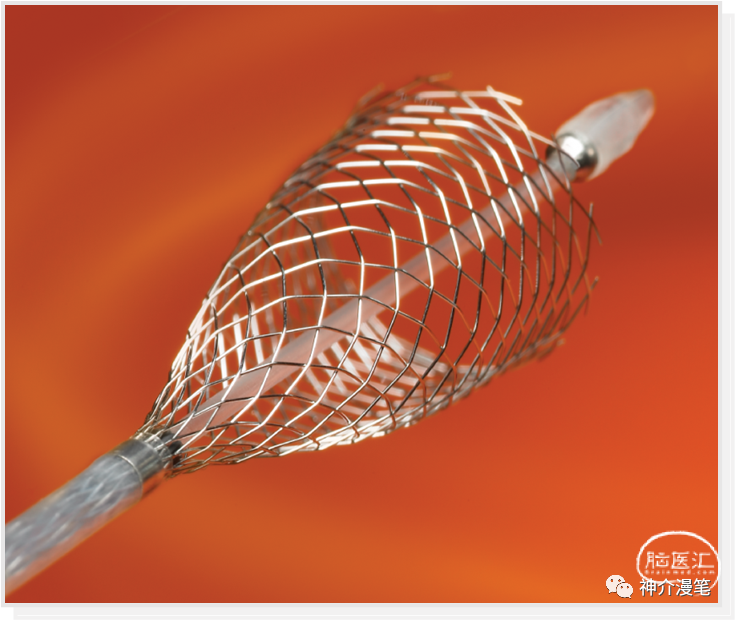

大神的脚步永不会停歇。1989年,Klaus Mathias在一位65岁患者的球扩时出现内膜撕脱。使用10*40的Wallsent支架进行补救。第一个颈动脉支架诞生了。需要提醒大家注意的是,在当时的年代,该支架是用于胆管手术的,并非为了颈动脉而生。当然我到现在也认为这是大神蓄谋已久的计划,而非偶然临时起意。在此后的十年间,逐渐意识到介入手术这玩意也还靠谱的人们,开始大量尝试介入治疗颈动脉狭窄,而球扩支架Palmaz成为了颈动脉支架的主力军。

闭环支架的设计特点和开环支架刚好相反,所有的支架单元都呈现出连续封闭的状态,整个支架为一个连续完成的整体。其设计的特点使得其网眼更小,更利于提高局部金属覆盖率与对斑块的保护。但是其在迂曲血管的贴壁性会略差,同时因为其作为一个整体存在的特点,其趋势是使血管变直。因此对于血管走形的改变会略大。下图为闭环支架的设计特点,可以看到所有支架网格均为封闭连续的结构。

Wallstent支架不同于前面两款,自身特点同样突出,关键词:编织支架,闭环支架,自膨支架,是目前主流颈动脉支架中唯一一款编织支架。具备着编织支架普遍共性,在不同管径血管内会被拉伸和短缩,释放难度略高于其他几款支架,但是有更高的金属覆盖率和更小的网眼面积。此外,wallstent支架的显影性是最棒的,这一点用过的可能都知道。